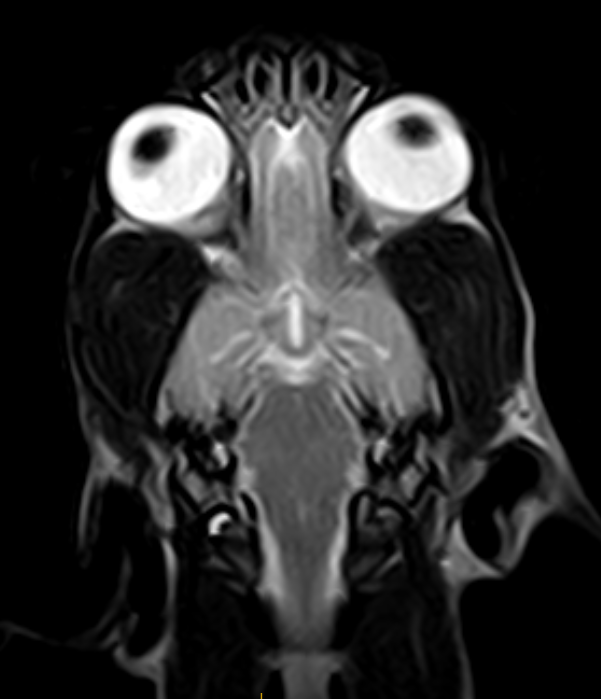

IMÁGENES CLÍNICAS

En la sección de imágenes clínicas, destacamos la precisión y claridad de nuestros estudios, respaldados por un equipo de radiólogos especializados en medicina veterinaria. Nos enorgullece ser un aliado confiable para veterinarios y clínicas, brindando un servicio rápido y eficiente para ayudar en la toma de decisiones clínicas fundamentadas.

Utilizamos resonancia magnética para obtener imágenes detalladas de tejidos blandos, articulaciones y el sistema nervioso central, permitiendo diagnósticos más precisos.